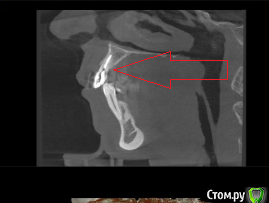

Евгений Ходыкин Опубликовано 19 марта, 2019 Автор Поделиться Опубликовано 19 марта, 2019 Общая аксиальная картина и сагиттальные срезы по 2.2, 2.3 Ссылка на комментарий

___49___ Опубликовано 19 марта, 2019 Поделиться Опубликовано 19 марта, 2019 Интересует этот отдел , полное КТ у вас интернет не позволяет скинуть ? Ссылка на комментарий